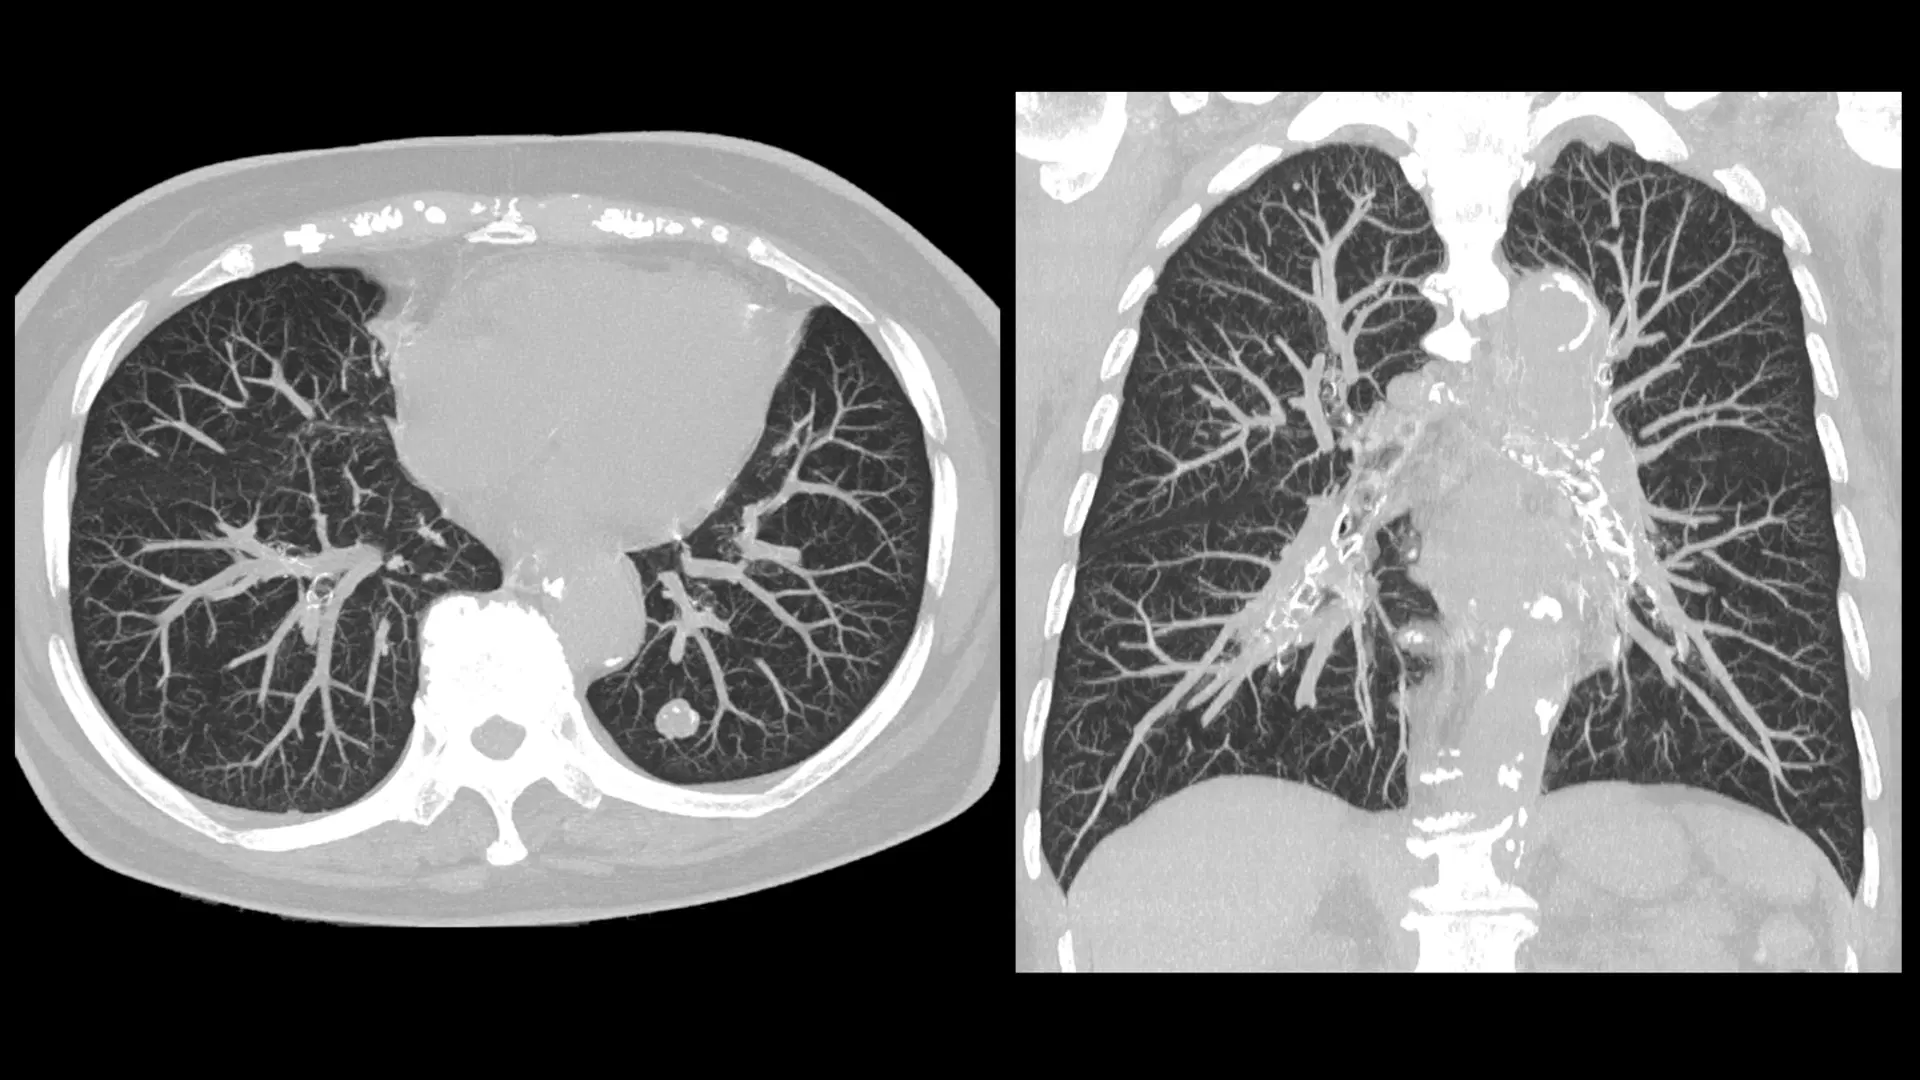

Chest CT Scan Lungs & Heart Imaging Identifies infections, tumors, pulmonary embolisms, and thoracic issues.